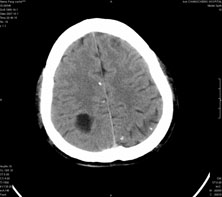

男,41岁,间断抽搐1小时,失神5分钟,bp130/90mmhg。低密度区ct值约16hu。

脑实质见多发散在的钙化点,左顶叶见一囊变灶,多考虑脑囊虫。

脑实质见多发散在的钙化点,右颞、顶叶见囊性灶,考虑脑囊虫。

多发的囊泡(多发囊型)+多发的钙化(慢性钙化型)=混合型

顶叶最大的囊直径2.2cm,如果考虑囊虫的话,囊是不是有点儿太大了?